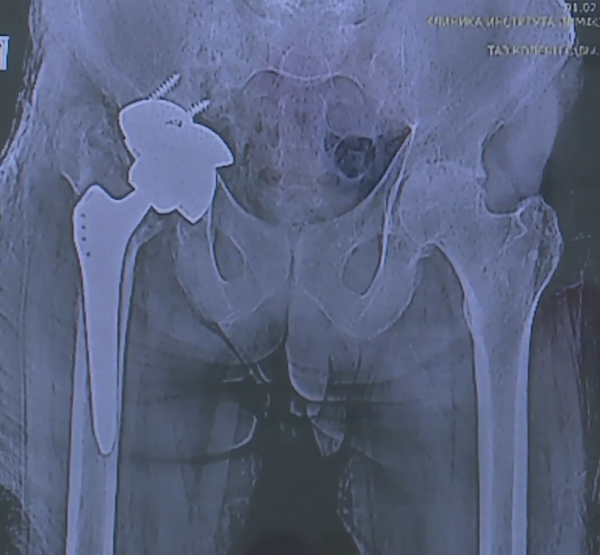

Операция по замене суставов, которая многих ставит на ноги, имеет свои подводные камни.

«Самым частым осложнением является развитие перипротезной инфекции. Пришла идея поместить антимикробный пептид в костный цемент, который используют для крепления протеза», ─ рассказала заведующая молодежной лабораторией НИИ клинической и экспериментальной лимфологии Наталья Бондаренко.

Профилактику инфекций закладывают еще на этапе операции. Главный герой истории – пептидомиметик – искусственно созданное вещество, разработка молодежной лаборатории НИИ клинической и экспериментальной лимфологии.